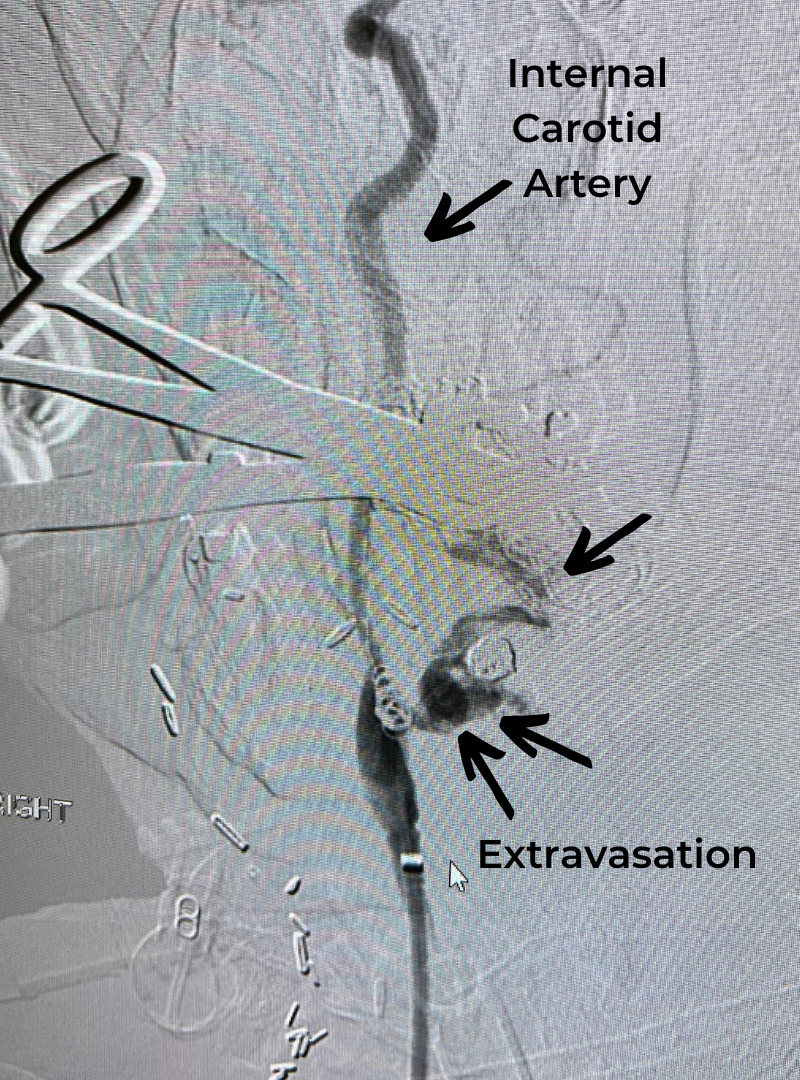

Midline anterior cranial fossa meningiomas are rare, and classified according to their anatomical site of origin. This includes the olfactory groove, planum sphenoidale, and tuberculum sella. Although they are benign and slow growing, they can invade the skull base and ethmoid sinus. Primary blood supply is usually from the anterior and posterior ethmoidal arteries. They are most often found in women, in their 5th and 6th decades of life. They commonly present with cognitive impairment and behavioral changes, which can be mistaken for early onset dementia or depression. Headaches, visual changes, and anosmia may also be present. Surgical resection generally reverses the cognitive and behavioral changes, and can be curative if gross total resection is attained.